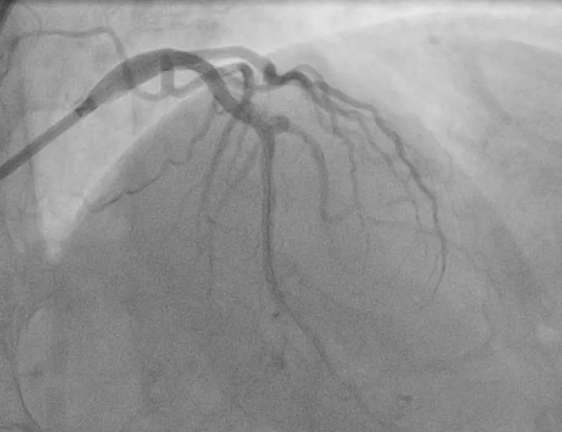

消毒、穿刺、送入导管,按照制定的程序一步步紧张而有序地进行,通过检查发现,老太太左前降支血管存在360度钙化,使用震波球囊对钙化病变多次治疗,钙化环充分断裂,经球囊扩张效果明显,随后,顺利植入支架。原本被“石头”堵塞的血管重新被扩张,恢复了血流,王老太的“心头”难题得以解决。